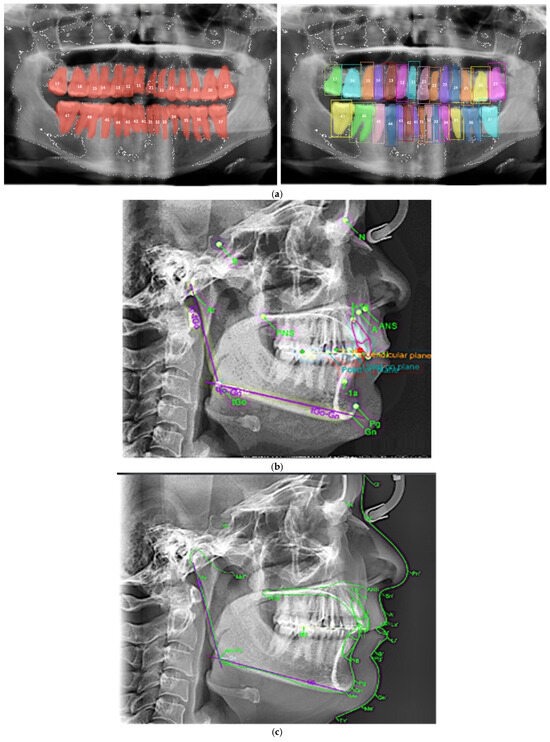

- Machine learning approaches for medical image analyses;